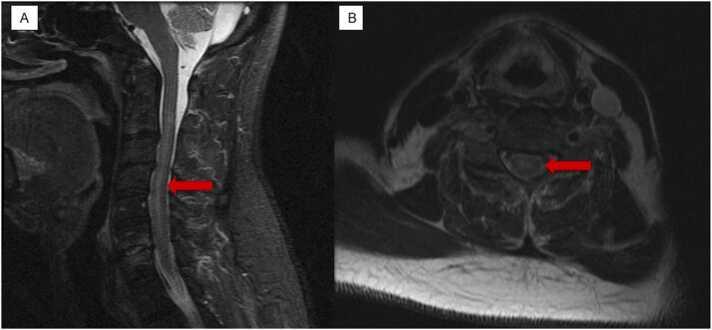

Acute transverse myelitis is a neurological disorder that leads to acute spinal cord injury due to inflammation caused by autoimmune disorders or by parainfectious etiologies. Among the many different infectious causes of transverse myelitis, one of the rare ones is Lyme disease. Here we describe a case of a 62 year old male who presents with bilateral paresthesia and weakness. MRI imaging of the cervical and thoracic spine led to the initial diagnosis of cervical cord edema leading to the symptoms associated transverse myelitis. However further workup of different infectious causes lead to positive Lyme titers with positive confirmatory ELISA testing. Initiation of Lyme disease treatment with IV ceftriaxone led to the gradual resolution of the symptoms.

急性横贯性脊髓炎是一种神经系统疾病,由于自身免疫性疾病或感染后病因引起的炎症导致急性脊髓损伤。在横贯性脊髓炎的众多不同感染原因中,莱姆病是罕见原因之一。在此,我们描述一例62岁男性患者,其表现为双侧感觉异常和无力。颈椎和胸椎的MRI成像初步诊断为颈髓水肿,导致出现与横贯性脊髓炎相关的症状。然而,对不同感染原因的进一步检查发现莱姆病滴度呈阳性,ELISA检测确诊。静脉注射头孢曲松治疗莱姆病后,症状逐渐缓解。